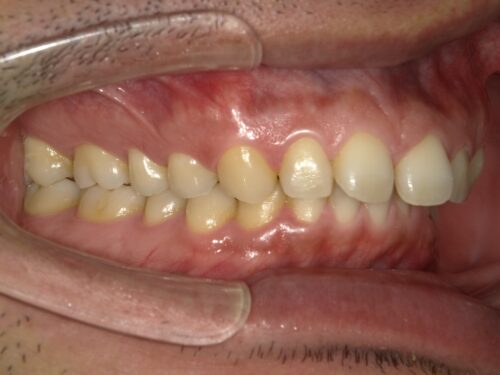

口腔内写真です。

全体的には歯並びは悪くないが、前歯のすき間と少し前に出ていることが少し気になるとのことです。

以前から気になってはいたが、ワイヤーつけての矯正には抵抗があり、今回マウスピース矯正について教えてほしいとの希望です。